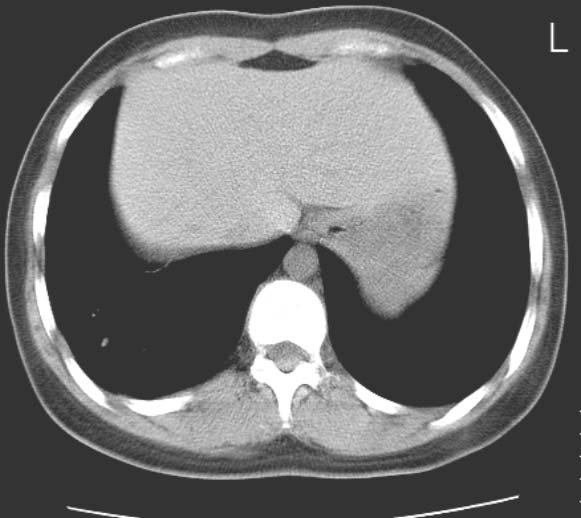

标题: CT25816:胸部CT,请会诊。

女 19岁,发热,咳嗽

右肺下叶支扩伴感染。

典型的支气管粘液栓,建议抗炎治疗复查,会有变化的。

考虑右肺下叶支气管扩张并黏液嵌塞。